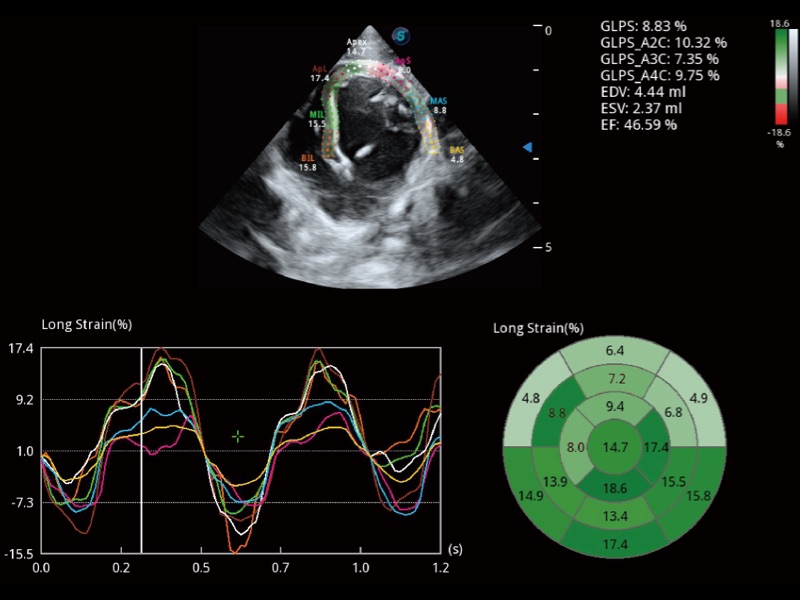

具備多種協(xié)議可選,同時(shí)支持17階段劃分法和專業(yè)的SE報(bào)告。

通過360度任意調(diào)節(jié)3條M型取樣線,在同一心動周期上觀察心臟不同位置的運(yùn)動曲線,得到準(zhǔn)確的心功能測量數(shù)據(jù),有效評估心肌運(yùn)動及左心室功能。